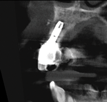

In this case, a dental implant that had been placed 10 years prior was functional, stable, and esthetically acceptable to the patient. However, a significant fistula was present on the facial-apical aspect of the ridge in the maxillary lateral incisor area. This area was painfully sensitive to touch and demonstrated purulence when squeezed. To evaluate the lesion, first, a conventional digital radiograph was acquired, which revealed an apical radiolucency at the apex of the implant (Figure 1). Further analysis using cone-beam computed tomography (CBCT) demonstrated a fistula from that site to the oral environment (Figure 2). Treatment options were discussed, including removal of the implant, followed by grafting, a healing period, and replacement of the implant and implant-retained crown. If this option was selected, a transitional appliance would need to be created. Another option was to attempt to salvage the implant and implant crown by treating the infection and grafting the site to create a new boney wall and eliminate the fistula. Ultimately, the patient accepted this option to attempt to salvage the fixture and crown.

Peri-implantitis was not the culprit behind the creation of this infected site; the lesion developed as a result of the position of the implant. Although the implant was initially stable upon placement, it was angled such that its apex had penetrated through the facial plate of bone. Without a sagittal CBCT analysis or a releasing flap performed to evaluate the initial placement, the surgeon could easily miss this. Regardless, the circumstances warranted evaluation of the apical aspect of the implant to attempt to salvage it.

(2.) Preoperative CBCT analysis demonstrating a fistula from the site of the radiolucency to the oral environment.

Figure 2